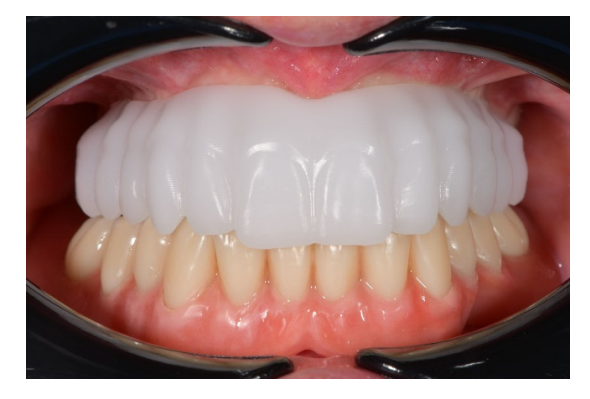

После этого эстетическая примерка была снята. Четыре новые скан-аналоги были подключены к временным абатментам и отсканированы вне рта пациента с помощью обычного экстраорального сканера (Рисунок 21). Прежде чем была изготовлена окончательная CAD/CAM конструкция, клинически и радиографически была протестирована радиопрозрачная алюминиевая конструкция. После этого было выполнено перекрестное монтаж окончательной реставрации (позиция имплантата) с функционализированной временной реставрацией, а также с оригинальным планом. На следующем приеме титановая CAD/CAM конструкция была протестирована в рту пациента. В конце концов, была доставлена фиксированная, удерживаемая винтом, имплантоподдерживаемая реставрация, изготовленная из титана, с композитом в качестве облицовочного материала (Рисунки 22–24). Композит был выбран из-за своей прочности и способности к поглощению ударов. Лингвализированный окклюзия была спроектирована для всех окончательных реставраций, с использованием анатомических зубов для верхнего протеза и модифицированных неанатомических или полуанатомических зубов для нижних протезов.

Все имплантаты успешно остеоинтегрировались, и все окончательные протезы функционировали к концу данного предварительного отчета, что привело к 100% выживаемости имплантатов и протезов. Не было зафиксировано биологических и технических осложнений. Однако одна из пяти оттисков была выполнена повторно из-за неточности алюминиевой ложки. В этом случае алюминиевая ложка была разделена, и две части были зафиксированы с использованием специальной светокурящей смолы для имплантатов (EZ-Pattern LC), полимеризованной под УФ/ВИЗ светом 350–480 нм. Кроме того, был сделан гипсовый оттиск. После доставки окончательных реставраций механических осложнений не наблюдалось. Все пациенты были полностью удовлетворены как функциональными, так и эстетическими результатами и были готовы повторить процедуру снова.